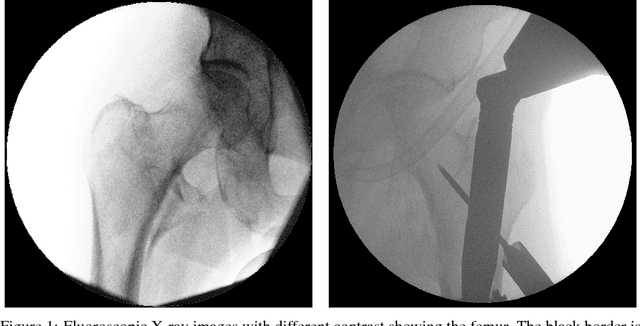

We propose approaches based on deep learning to localize objects in images when only a small training dataset is available and the images have low quality. That applies to many problems in medical image processing, and in particular to the analysis of fluoroscopic (low-dose) X-ray images, where the images have low contrast. We solve the problem by incorporating high-level information about the objects, which could be a simple geometrical model, like a circular outline, or a more complex statistical model. A simple geometrical representation can sufficiently describe some objects and only requires minimal labeling. Statistical shape models can be used to represent more complex objects. We propose computationally efficient two-stage approaches, which we call deep morphing, for both representations by fitting the representation to the output of a deep segmentation network.